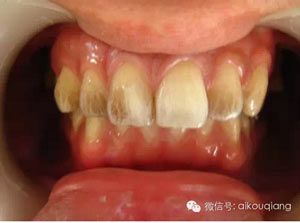

男性成年人喜歡喝茶、抽煙,造成牙齒表面色素沉著,很不美觀

2.jpg

洗牙(潔治)后,潔白如一

6.jpg